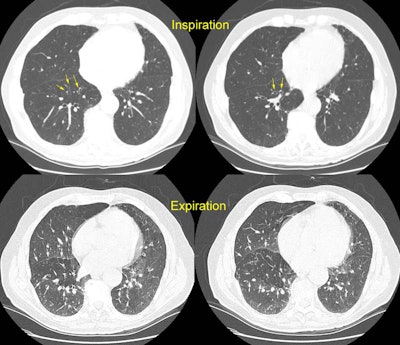

Bronchiolitis obliterans:

The patient shown below had experienced a severe right lower lobe haemophilus influenza pneumonia the preceding year, but had persistent pulmonary complains. The inspiratory CT images reveal bronchiectatic changes involving the bronchi to the anterior and medial basal segments of the right lower lobe (yellow arrows). Expiratory images deomstrate air trapping in these same segments (white arrows). Air trapping is also evident in the medial segment of the right middle lobe. The findings are consistent with post-infectious bronchiolitis obliterans.